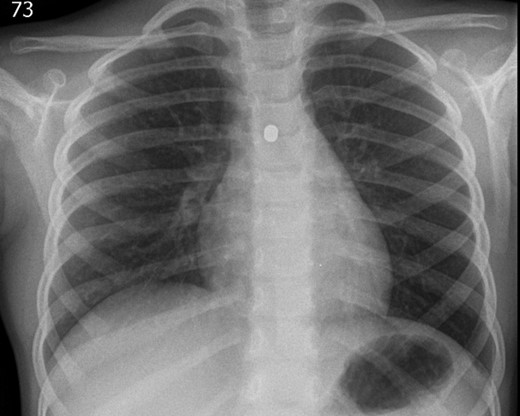

A ventilating bronchoscopy was performed by the otolaryngology team where the FB was found to be stuck to the posterior wall of the left main bronchus. The FB was left in-situ. After the operation, a lateral CXR (Fig. 3) illustrated the metallic FB appeared to be two spherical balls, with the anterior one in the left main bronchus and the posterior one in the oesophagus. A subsequent further history from the parents suggested these were from the older sibling’s toys.

Lateral CXR showed the metallic foreign body to be two spherical balls, with the anterior one in the left main bronchus and the posterior one in the oesophagus.